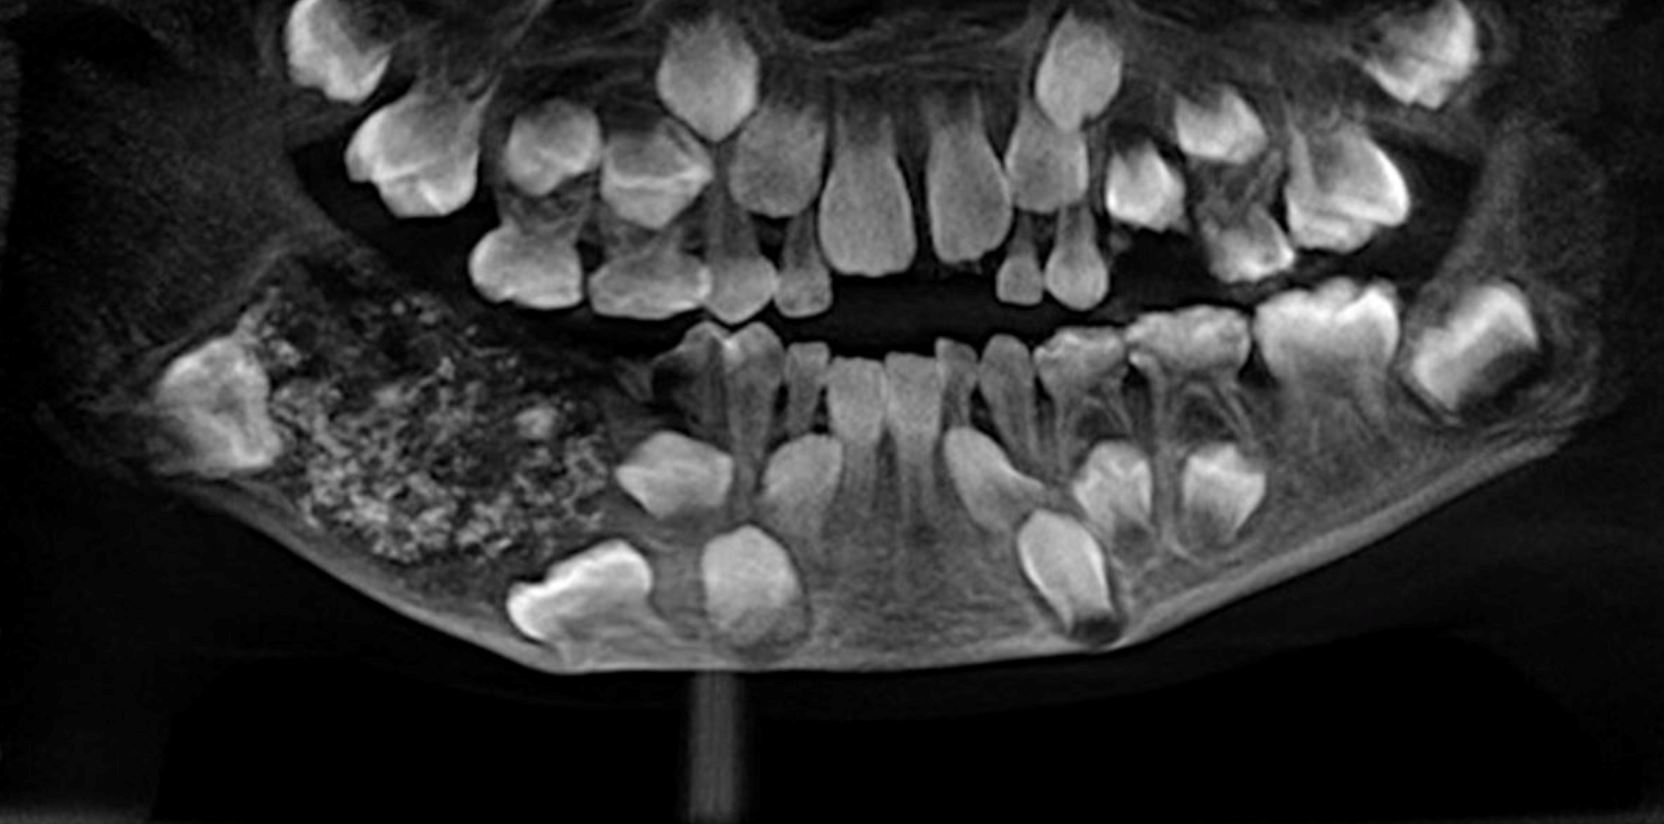

Doktor yang membedah kanak-kanak ini akhirnya menemui punca kepada rasa sakit itu selepas menemui beberapa struktur keras yang tumbuh dalam rahangnya.

“Struktur seperti gigi itu terdapat dalam beberapa saiz antara 0.1 milimeter (mm) dan 15 mm. Ia kelihatan seperti mutiara dalam tiram. Struktur itu juga mempunyai akar dan lapisan enamel seperti gigi, “ kata Dr Pratibha Ramani.